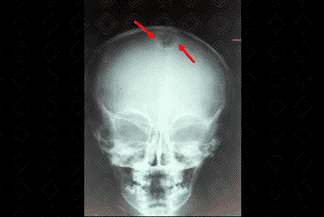

Texto alternativo para a imagem Figura 1. Crédito: Dra. Elazir Mota - Rio de Janeiro/RJ

Texto alternativo para a imagem Figura 2. Crédito: Dra. Elazir Mota - Rio de Janeiro/RJ

Descrição da lesão: Cisto dermoide. Radiografia de crânio AP e perfil (figuras 1 e 2): lesão ovalada, bem definida, na linha média, adjacente à sutura sagital e metópica.

• Radiografia do crânio: Lesão ovalada, bem definida, em geral adjacente as suturas;